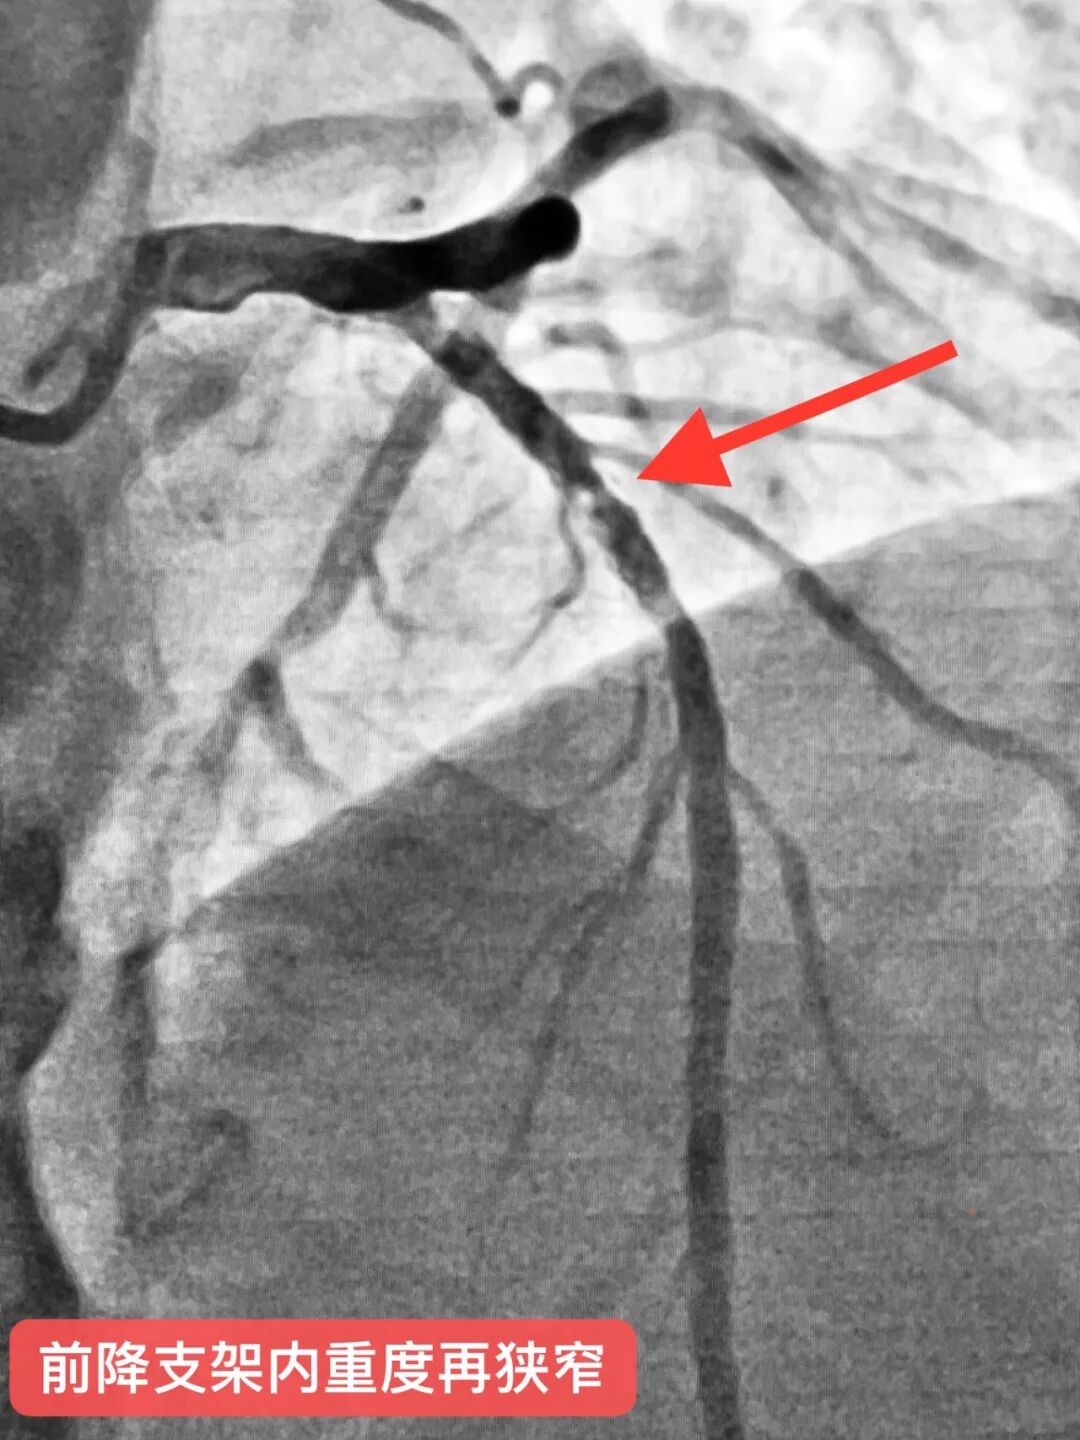

导读 心脏介入无植入,“药物球囊”显奇效!近日,县域首例支架内再狭窄药物球囊扩张术在玉山中医院顺利完成。 患者汪老伯,8年前因急性心梗在外院于前降支植入一枚支架,近一年反复出现胸闷、胸痛不适症状来县中医院就诊。经评估后考虑支架再狭窄可能,复查冠脉造影提示原支架内重度再狭窄。如在原支架内狭窄处叠加支架可能会明显增加再次狭窄风险,并且对血管弹性有明显影响,药物球囊扩张术是所有指南的优先推荐。经心脏介入科徐承权手术团队充分讨论并告知患者家属病情后,决定采用DCB(药物球囊)技术处理。术后患者症状即刻改善,立竿见影,3天后康复出院。